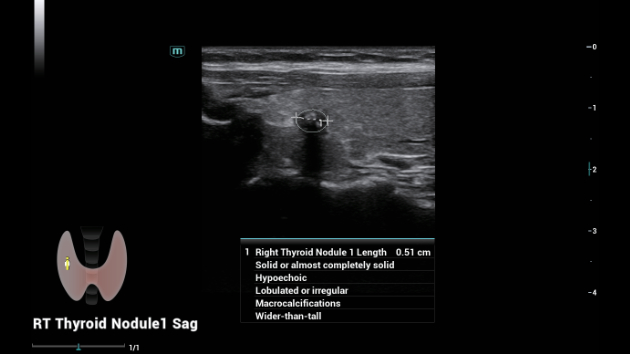

De Consona biedt nieuwe en concrete oplossingen die effici?nt helpen bij het stellen van een vlotte diagnose voor veel verschillende soorten pati?nten.

Ongeacht of u werkzaam bent in een ziekenhuis of kliniek, of uw vaardigheden aanscherpt op het gebied van algemene beeldvormingstoepassingen, vrouwengeneeskunde of cardiovasculaire specialismen, in deze serie vindt u zeer krachtige hulpmiddelen waarmee u aan kop kunt blijven.